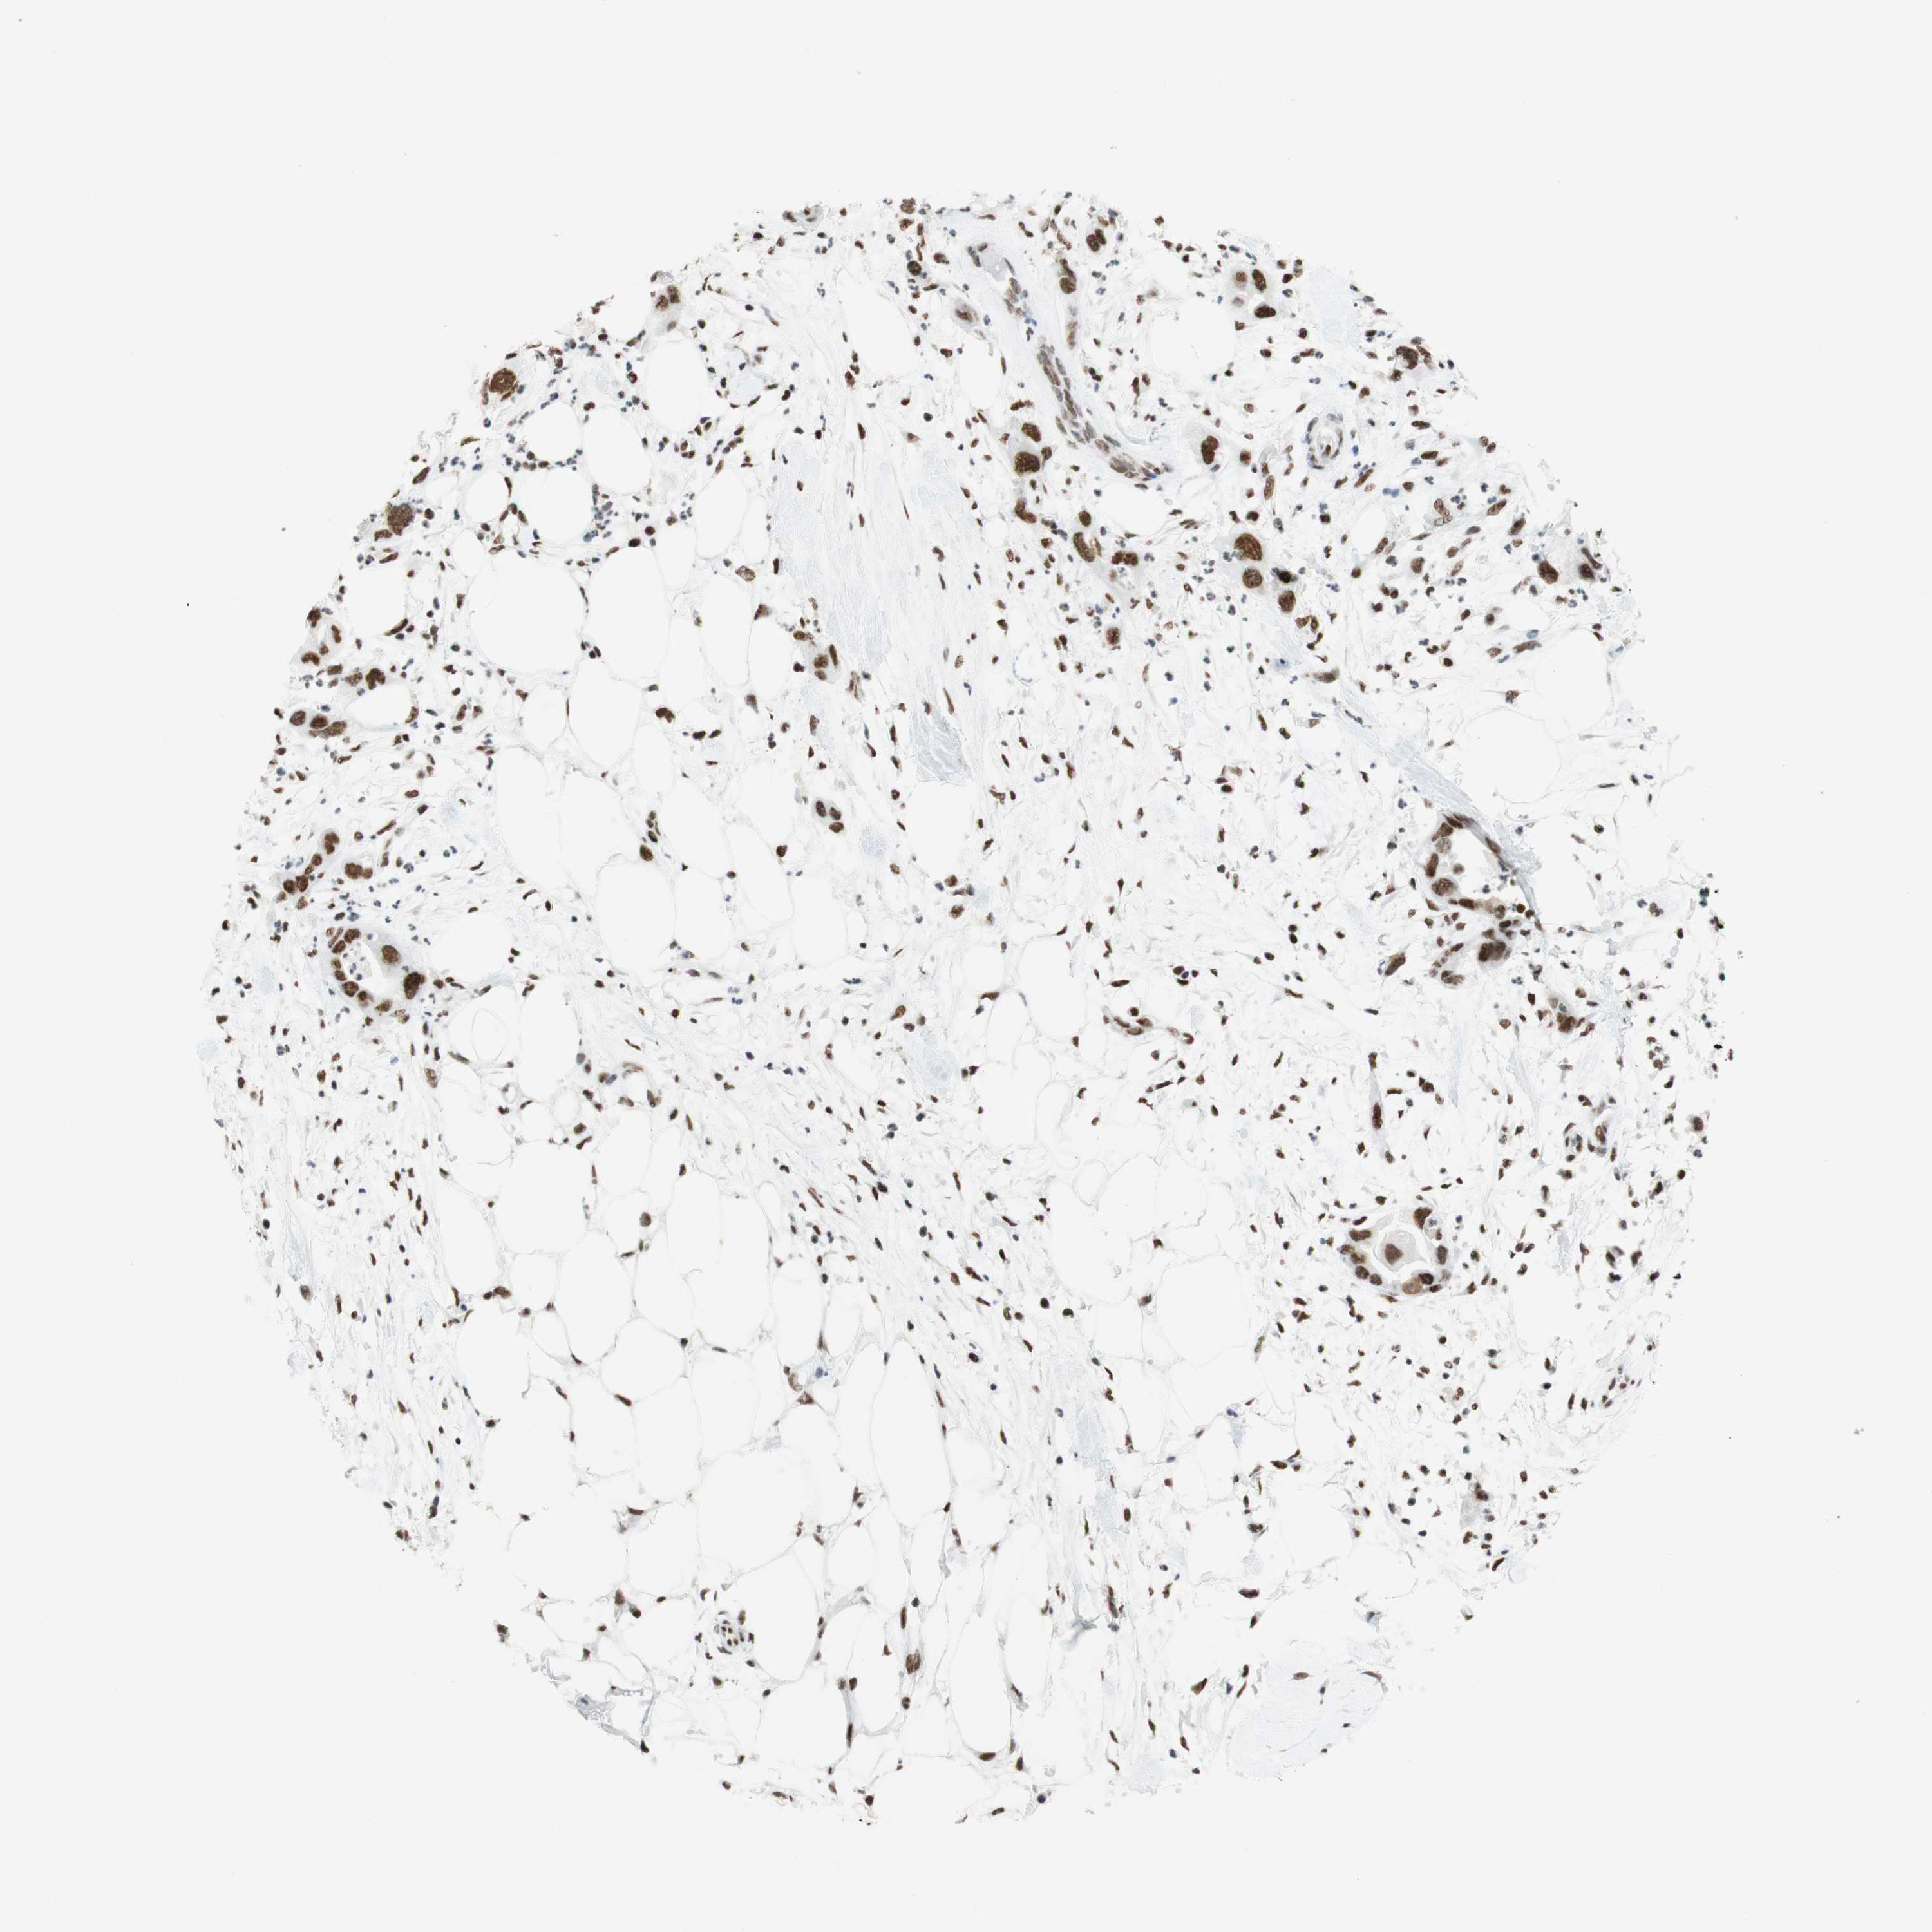

PANCREATIC CANCER - Protein expressioni

A mouse-over function shows sample information and annotation data. Click on an image to view it in a full screen mode. Samples can be filtered based on level of antibody staining by selecting one or several of the following categories: high, medium, low and not detected. The assay and annotation is described here.

Note that samples used for immunohistochemistry by the Human Protein Atlas do not correspond to samples in the TCGA dataset.

Antibody stainingi

Antibody staining in the annotated cell types in the current human tissue is reported as not detected, low, medium, or high, based on conventional immunohistochemistry profiling in selected tissues. This score is based on the combination of the staining intensity and fraction of stained cells.

Each image is clickable and will lead to virtual microscopy that enables deeper exploration of all samples and also displays staining intensity scores, fraction scores and subcellular localization as well as patient and tissue information for each sample.

Antibody CAB012478

Adenocarcinoma, NOS

Adenocarcinoma, metastatic, NOS